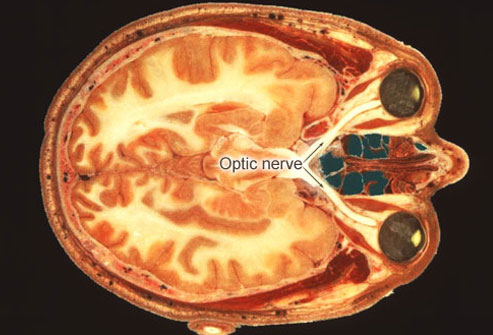

Προβλήματα όρασης

Πάνω από το 50% των ασθενών με σκλήρυνση αντιμετωπίζει μια πάθηση που ονομάζεται οπτική νευρίτιδα. Σε αρκετές περιπτώσεις, τα προβλήματα όρασης αποτελούν το πρώτο σύμπτωμα της σκλήρυνσης.